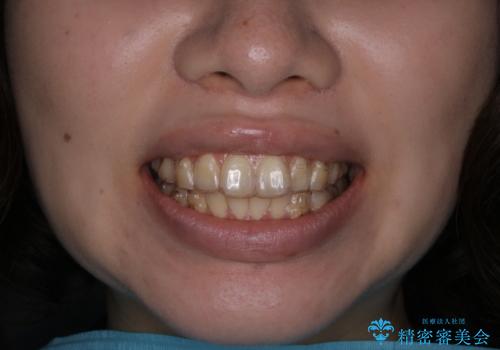

インビザラインでの治療中の患者様のクリーニング前後写真です。

- インビザライン矯正中に茶色が気になるとのことで来院されました。PMTC30分コースを行いました。